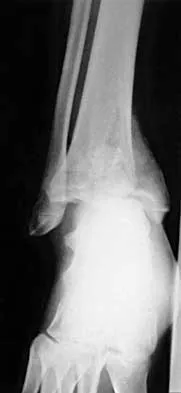

Figures 4a through 4c show the radiographs of a 43-year-old woman who sustained a twisting injury to her right ankle. She has ankle pain and tenderness medially and laterally. To help determine the optimal treatment, an external rotation stress radiograph of the ankle is obtained. This test is designed to evaluate the integrity of what structure?

In the presence of a supination external rotation-type fracture of the distal fibula (Weber type B), stability of the ankle is best assessed by performing an external rotation stress AP view of the ankle. This test is used to assess the integrity of the deltoid ligament. The presence of a deltoid ligament rupture results in instability and generally is best managed surgically. The gravity stress test can also be used. Egol KA, Amirtharajah M, Tejwani NC, et al: Ankle stress test for predicting the need for surgical fixation of isolated fibular fractures. J Bone Joint Surg Am 2004;86:2393-2398. McConnell T, Creevy W, Tornetta P III: Stress examination of supination external rotation-type fibular fractures. J Bone Joint Surg Am 2004;86:2171-2178.